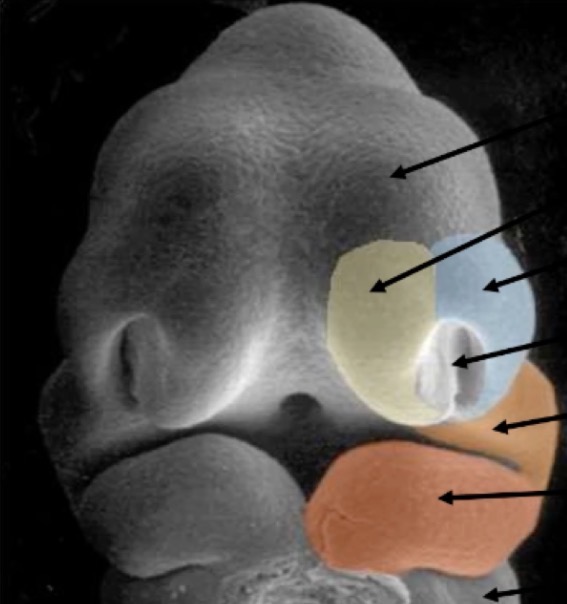

Mise en place de la cavité buccale

Entre la 4 et la 10 semaine de développement

Semaine 4 et 5

Semaine 6

Mise en place de la face

4eme semaine